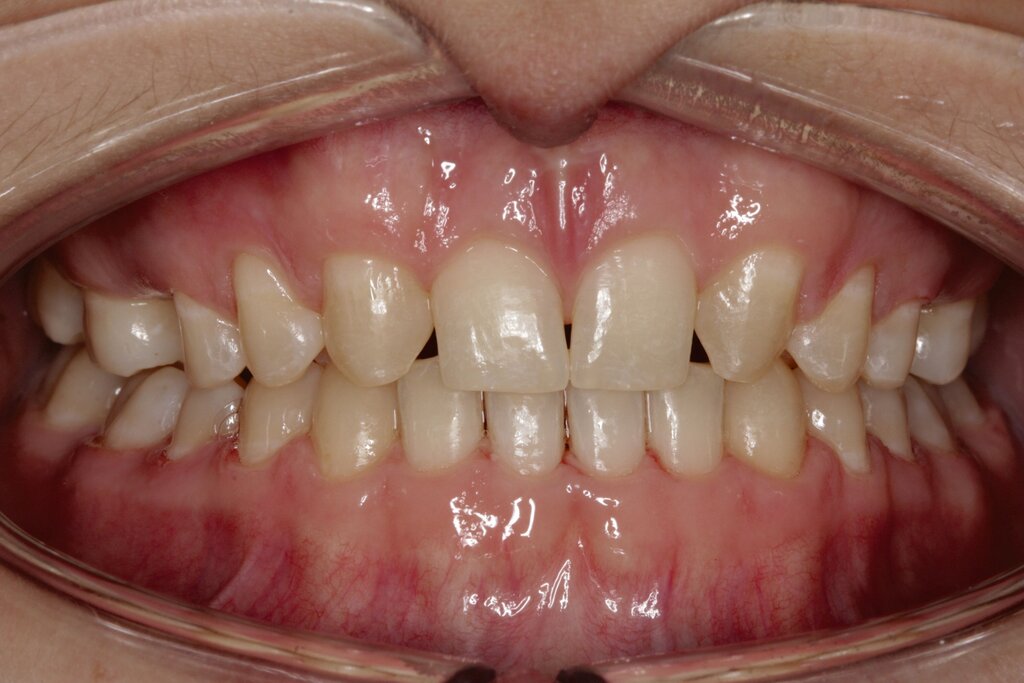

Im vorliegenden Fall stand der Zahn 23 bereits im Mesialstand bei hoher Lachlinie und tendenziell konkavem Lippenprofil. Bezüglich Morphologie und Farbe waren die Zähne 13 und 23 nicht ausgeprägt eckzahntypisch. Es bestand kein Platzmangel im Gegenkiefer. Die Patientin war bei der Erstdiagnose 12,5 Jahre alt und im Wechselgebiss der zweiten Phase mit atypischer Durchbruchreihenfolge. Es bestand eine geringfügige Klasse II. Der Overjet war vergrößert bei vertikaler Wachstumstendenz, der Overbite war um circa einen Millimeter vergrößert aufgrund der geringfügigen Steilstellung der Oberkiefer-Front. Es bestand der Verdacht auf Nichtanlage der Weisheitszähne, 15 und 25 waren verlagert.

Daher wurde ein Lückenmanagement mit Lückenschluss in der Oberkiefer-Front und Lückenöffnung mesial 16 und 26 außerhalb der ästhetischen Zone angestrebt. Eine implantatprothetische Versorgung kam aufgrund des jungen Alters der Patientin nicht infrage. Die Autotransplantation eines Prämolaren war ebenfalls ausgeschlossen, da kein Engstand und keine Indikation zur Ausgleichsextraktion bestanden.

Eine vollständige Mesialisation der Dentition im ersten und im zweiten Quadranten wurde von der Patientin zur Abkürzung der Behandlungsdauer nicht gewünscht. Ferner bestand der Verdacht auf Nichtanlage von 18 und 28, was bei einer vollständigen Mesialisation des ersten und des zweiten Quadranten zu einer fehlenden Abstützung von 37 und 47 führen kann. Der Rezessus der Kieferhöhle war rechts tief. Alternativ wäre in diesem Fall auch die Lückenöffnung in Regio 12 und 22 denkbar, allerdings dann mit einer prothetischen Restauration in der ästhetischen Zone bei hoher Lachlinie.